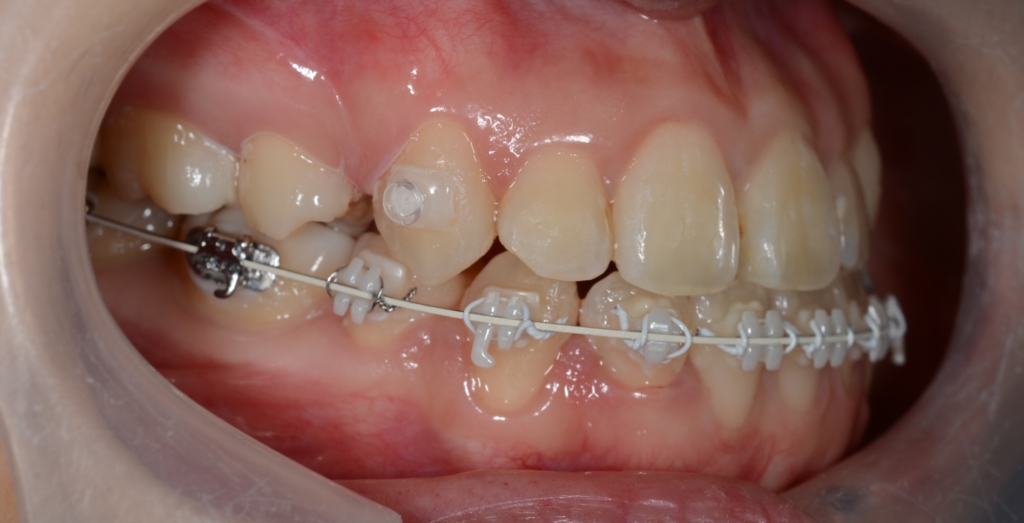

マルチブラケットシステム(ハーフリンガル type)で矯正を開始。

途中、早期の被蓋改善を図るため、上の奥歯から下の前歯へ引っ掛ける顎間ゴムを3か月間使用しています。

【1年経過】